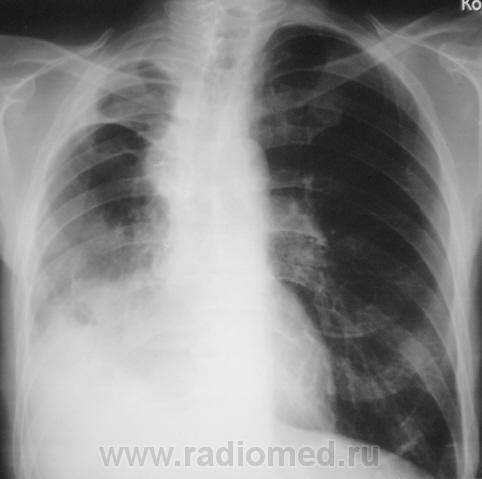

Просьба оценить динамику.

После лобэктомии.

Снимки - два этапа - до лобъектомии и после лобэктомии (верхняя доля) правого лёгкого).

Конечно, выставленное с такой манере может показаться весьма странным. Фактически это "хвост" случая, который закончился (на настоящее время) резекцией доли справа (верхняя). Хотя сейчас, многими докторами "высокой клиники" высказываются мнения, что все могло быть иначе, менее "кроваво", если-бы во-время и своевременно, и если-бы не тянули...